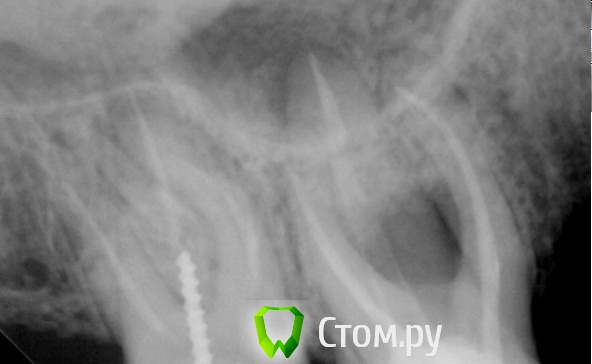

Kolchanov Опубликовано 13 сентября, 2014 Автор Поделиться Опубликовано 13 сентября, 2014 Как думаете, 6ку лучше сразу выдернуть или все-таки залезть и посмотреть? Смущает какой-то процесс между корнями. Планируется мост, но если удалять, то мосту уже не быть. Ссылка на комментарий

Shaid Опубликовано 13 сентября, 2014 Поделиться Опубликовано 13 сентября, 2014 (изменено) А семерка не смущает?) Изменено 13 сентября, 2014 пользователем Shaid Ссылка на комментарий

Kolchanov Опубликовано 13 сентября, 2014 Автор Поделиться Опубликовано 13 сентября, 2014 Семерку я пару часов назад разобрал уже. Ссылка на комментарий

M@estro Опубликовано 13 сентября, 2014 Поделиться Опубликовано 13 сентября, 2014 Думается,что 6 на выход. Ссылка на комментарий